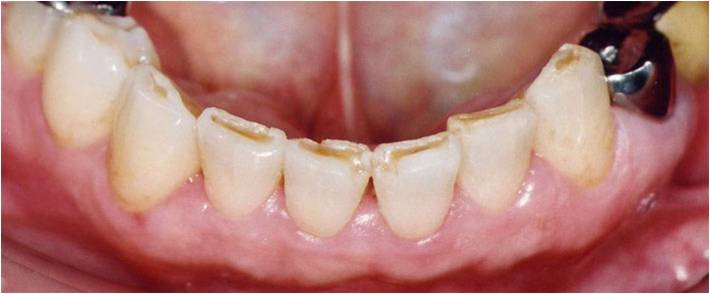

歯の摩耗・欠け

歯の表面のエナメル質が削れ、象牙質が露出して知覚過敏を引き起こします。

歯の先端が真っ直ぐに削れて、平らになっている。